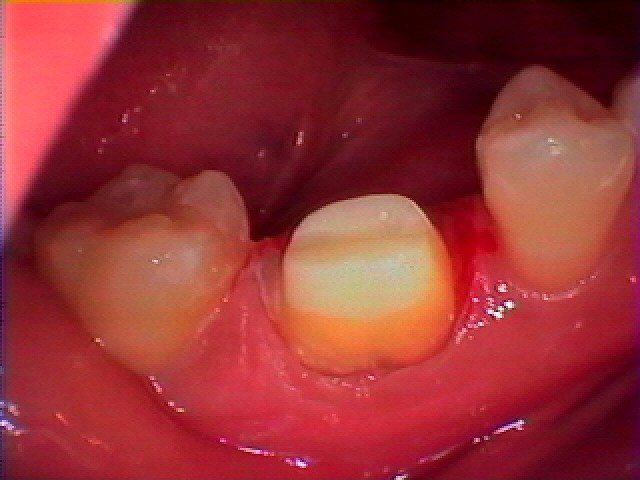

このように支台歯形成を行っています